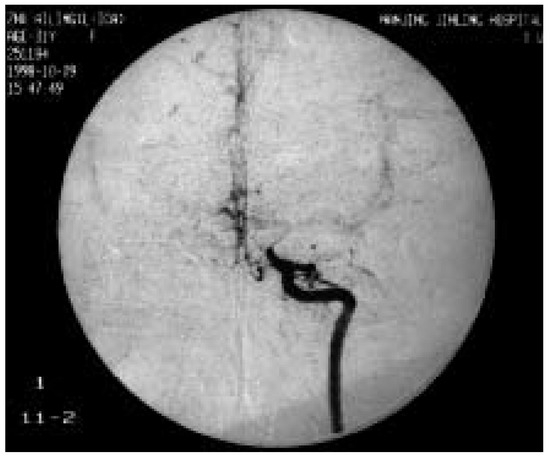

Rarely, adult moyamoya disease presents with recurrent migraine-like headaches during a long course.We report the case of a 31-year-old woman with moyamoya disease and migraine-like headaches, with a 13-year history. Physical examination showed no neurologic deficits. Magnetic resonance angiography (MRA) and digital subtraction [...] Read more.

Rarely, adult moyamoya disease presents with recurrent migraine-like headaches during a long course.We report the case of a 31-year-old woman with moyamoya disease and migraine-like headaches, with a 13-year history. Physical examination showed no neurologic deficits. Magnetic resonance angiography (MRA) and digital subtraction angiography (DSA) showed occlusion of the right internal carotid artery (ICA), severe stenosis of the left ICA, and abnormal vascular network at the base of the brain. The calcium channel blocker, nimodipine, was introduced in order to prevent further symptoms. After the introduction of nimodipine, no further headache, weakness and numbness of the left hand occurred in this patient. This suggests that migraine-like headaches may be caused by moyamoya disease and that nimodipine may have a beneficial effect on this condition. Full article